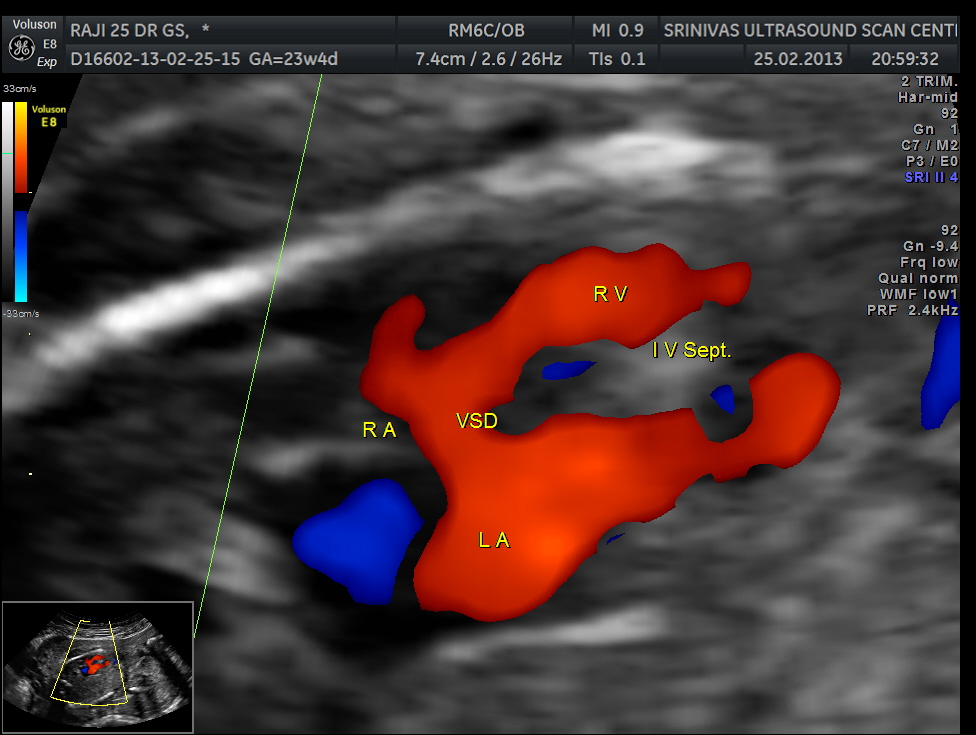

apart from foramen ovale flow , VSD is seen

Ventricular septal defect seen